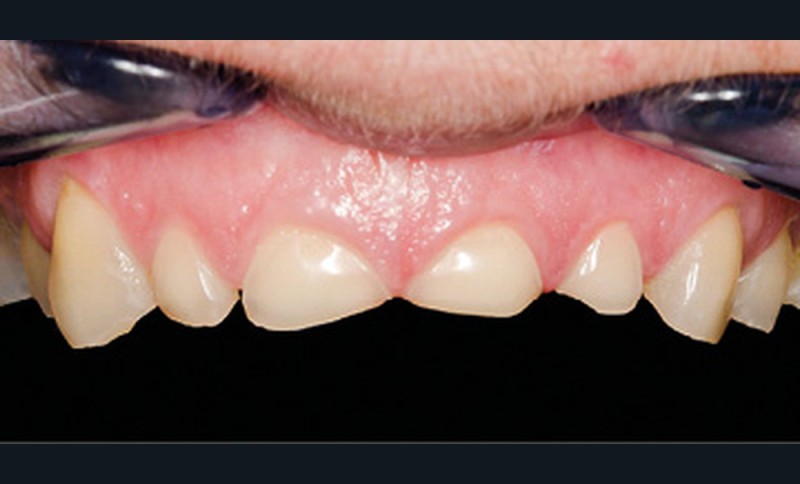

Mme V. est adressée au cabinet dentaire pour une réhabilitation de son sourire. À l’examen clinique, elle présente des usures sur l’ensemble de son maxillaire (fig. 17 et 18). Après évaluation du décalage OIM-ORC, une position de référence en relation centrée avec une dimension verticale augmentée est enregistrée. Pour valider cette position, il est demandé au laboratoire de réaliser un wax-up virtuel. Ce dernier est validé puis transféré en bouche pour essayage (fig. 19 et 20).

Ce mock-up est équilibré puis transformé en projet provisoire pour trois mois afin de s’assurer de la stabilité, du confort masticatoire et de l’esthétique. Au terme de ces trois mois, une empreinte de la situation est réalisée ainsi que l’enregistrement de l’occlusion ; enfin les secteurs postérieurs sont préparés pour recevoir des overlays. L’ensemble des informations (position et forme) est repris au sein du laboratoire pour dessiner les prothèses d’usage. Ces dernières seront produites par usinage, puis maquillées avant d’être envoyées au cabinet pour assemblage par collage sous champ opératoire (fig. 21 à 23).

Une fois les secteurs postérieurs et l’assise occlusale rétablis, le bloc incisivo-canin antérieur est préparé pour des restaurations adhésives. Là encore, l’assemblage se fait par collage sous champ opératoire. Le suivi est assuré pour contrôler la pérennité du traitement et une éventuelle reprise des usures. Pour ce faire, des rendez-vous cliniques avec réalisation d’une empreinte optique semestrielle sont programmés. La précision de l’empreinte permet ainsi de dépister le moindre phénomène d’usure (fig. 24 à 27).